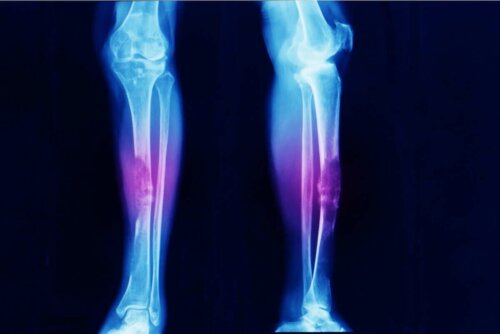

- الساركوما العظمية، هي سرطان العظام كما يشير اسمها.